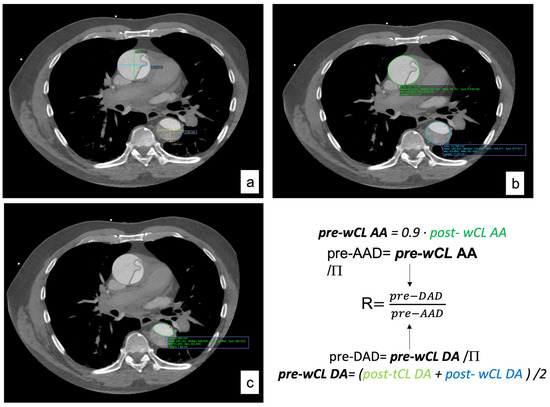

2.3. Imagining Analysis